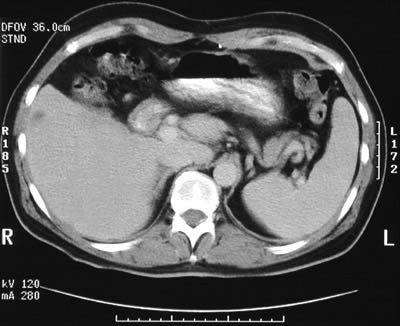

An abdominal CT scan later in the course reveals a solitary lesion in the liver.